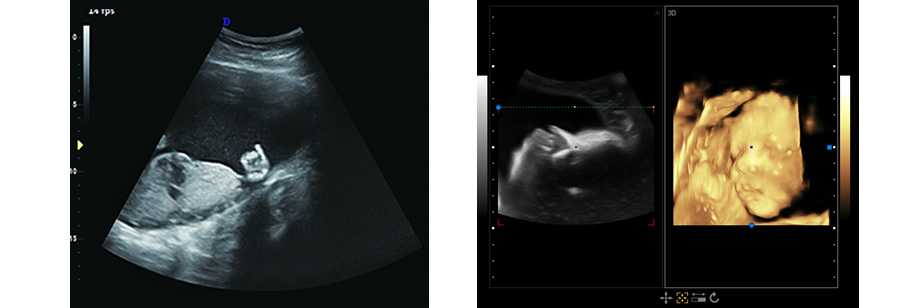

1.廣泛應用于腹部、泌尿科、婦產科、兒科/新生兒科、淺表組織、肌肉骨骼心臟等

立體光源成像 胎兒容貌實時顯示